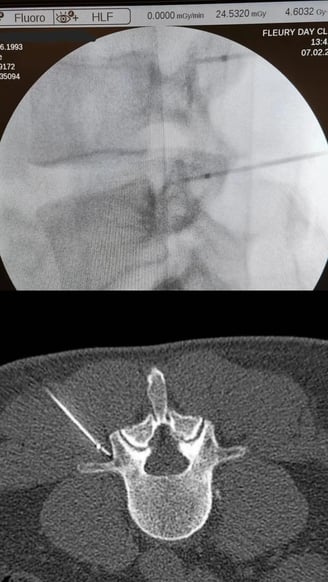

Biópsias Guiadas por Imagem (TC,USG ou Fluoroscopia)

Retirada de um fragmento de tecido vivo para determinação de um diagnóstico. Este procedimento é utilizado para inúmeras ocasiões na prática médica, como por exemplo para definir o diagnóstico de um tumor, determinar o seu tipo histológico e agressividade, documentar a existência de lesões metastáticas ou até mesmo para determinar a natureza de uma lesão (neoplásica ou infecciosa).